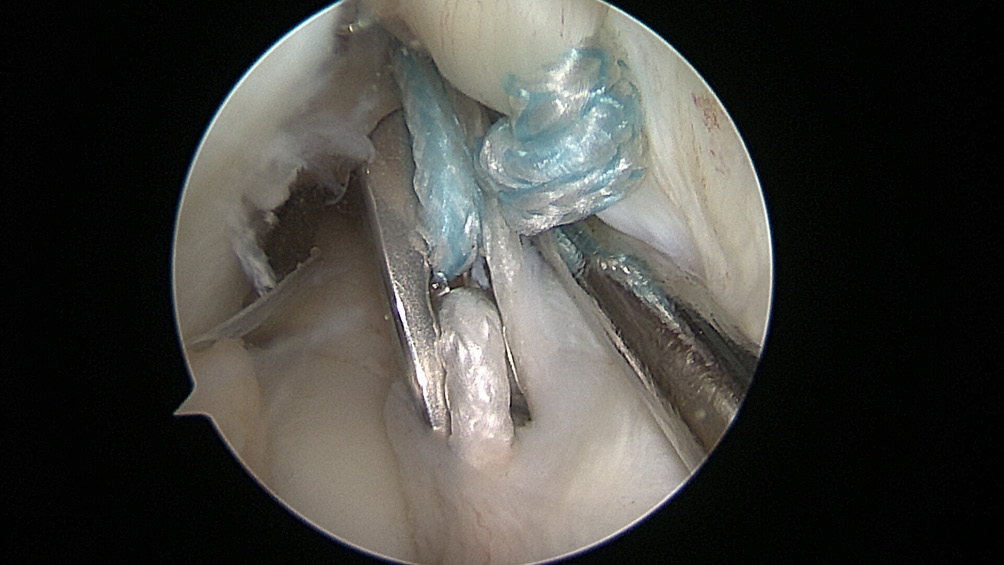

All the patients were operated on by the same team, using the same surgical technique and Neoligaments (Neoligaments) (Figure 1) or FiberTape (Biomet) (Figure 2) graft. It was fixed using Endobutton (Smith-Nephew, Watford, UK) on the femur and the interference screw, ComposiTCP30 (Biomet), on the tibia. It was prepared using the “outside-in” technique with the aimer device (Figure 3, Figure 4, Figure 5, Figure 6, Figure 7, Figure 8).